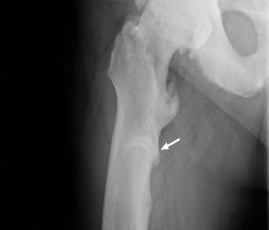

- Fémur : pseudo-fractures dans la région sous-trochantérienne du fémur droit et vers le centre de la diaphyse du fémur gauche; fracture de fatigue en voie de guérison au niveau du cortex médial du col fémoral gauche; enthésophytes et ostéoporose dans les deux hanches également notées (voir la radiographie 3)

44 ans : pseudo-fractures dans la région sous-trochantérienne du fémur droit et vers le centre de la diaphyse du fémur gauche; fracture de fatigue en voie de guérison au niveau du cortex médial du col fémoral gauche; enthésophytes et ostéoporose dans les deux hanches.